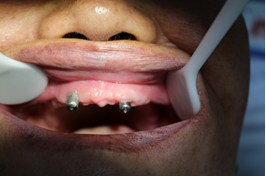

選復(fù)合基臺(tái)(上頜)/選復(fù)合基臺(tái)(下)

桿卡試戴(上頜)/桿卡試戴(下頜)

術(shù)后片/選復(fù)合基臺(tái)(下頜)

桿卡試戴(下頜)/活動(dòng)義齒(上頜)